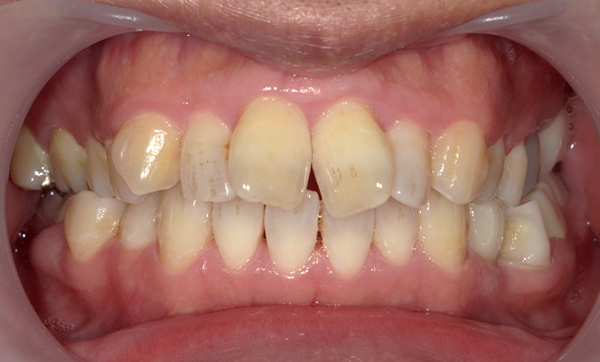

症例_013 前歯「八の字/V字型」症例

治療期間:8ヶ月金額:30万円+税20代女性八の字/V字型捻転歯上の前歯だけ